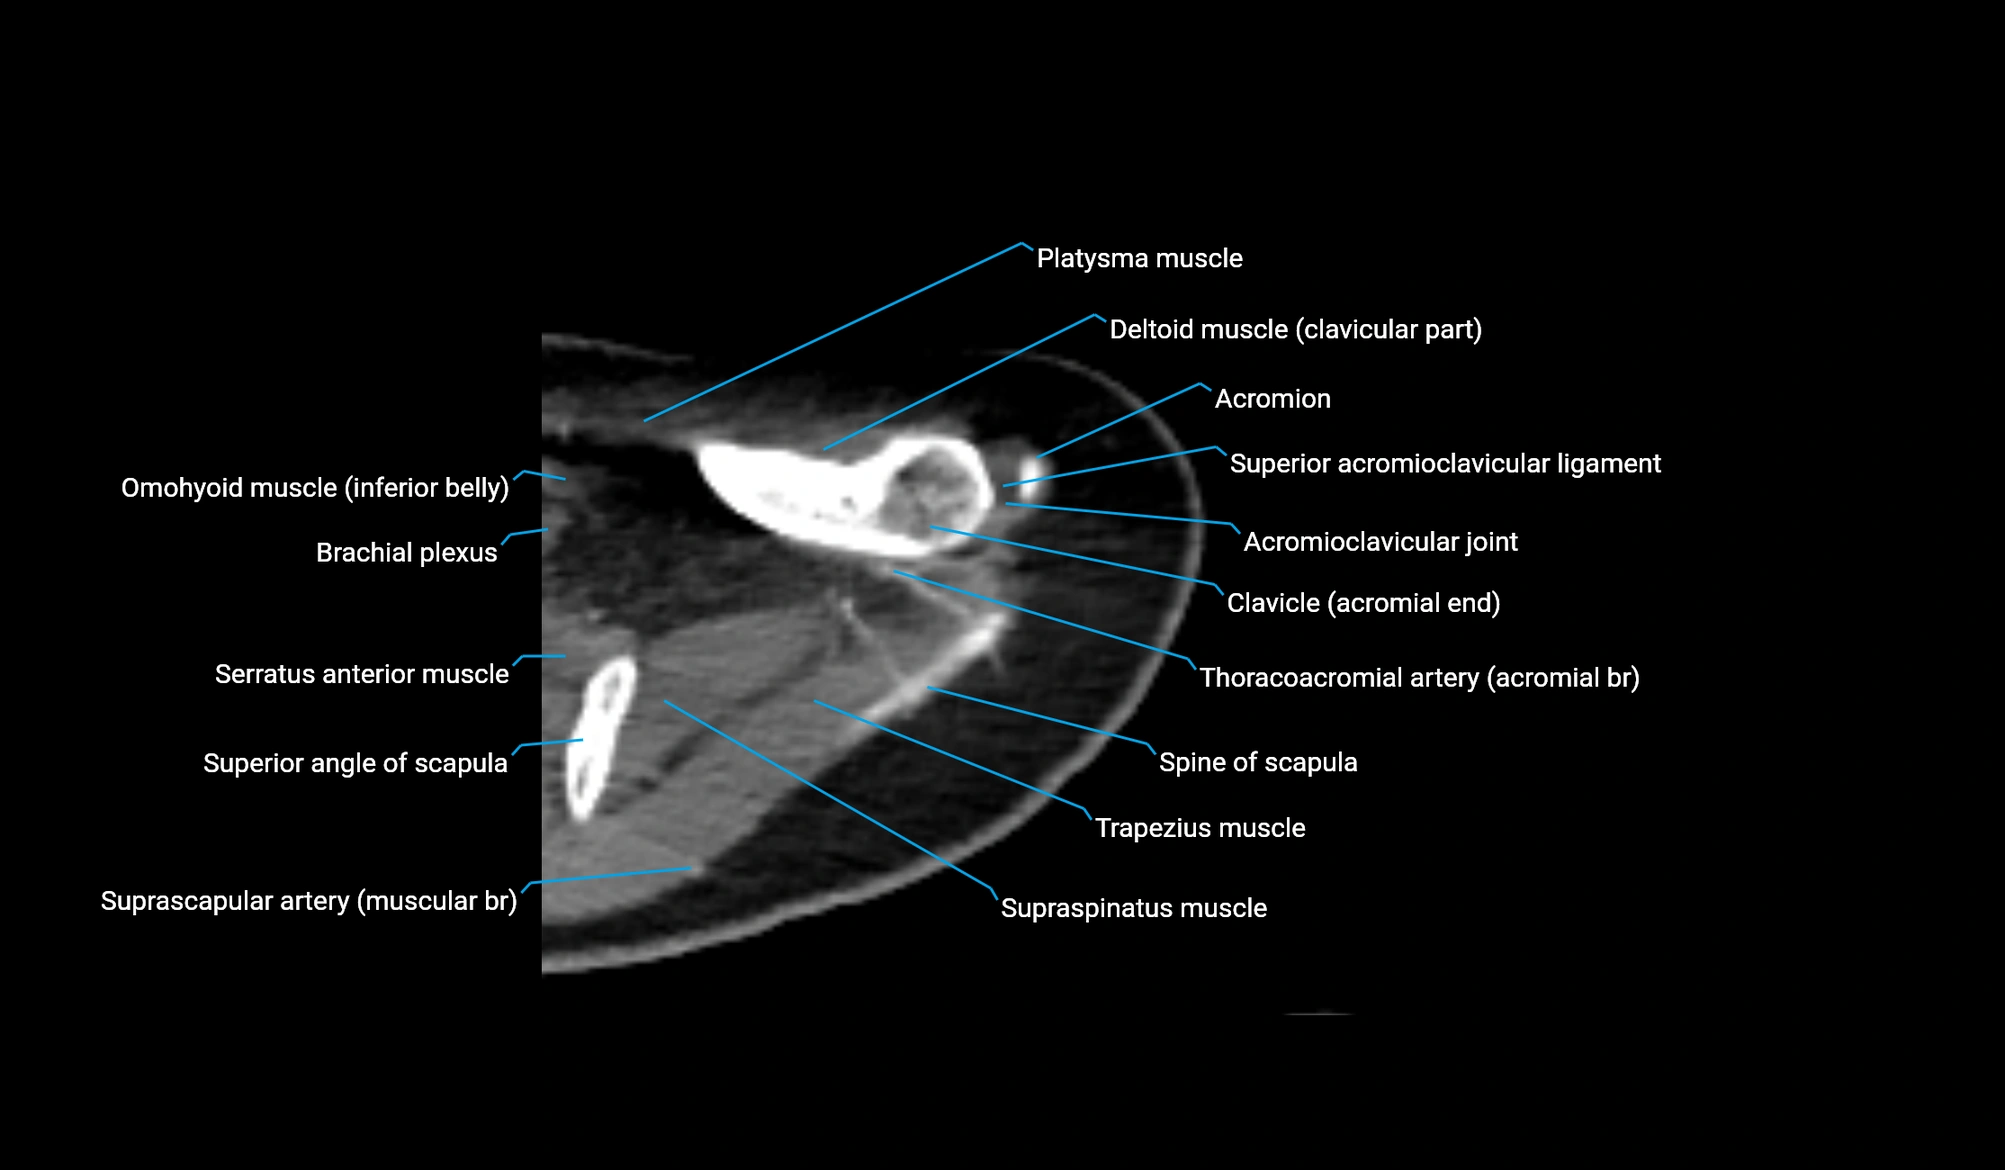

CT image